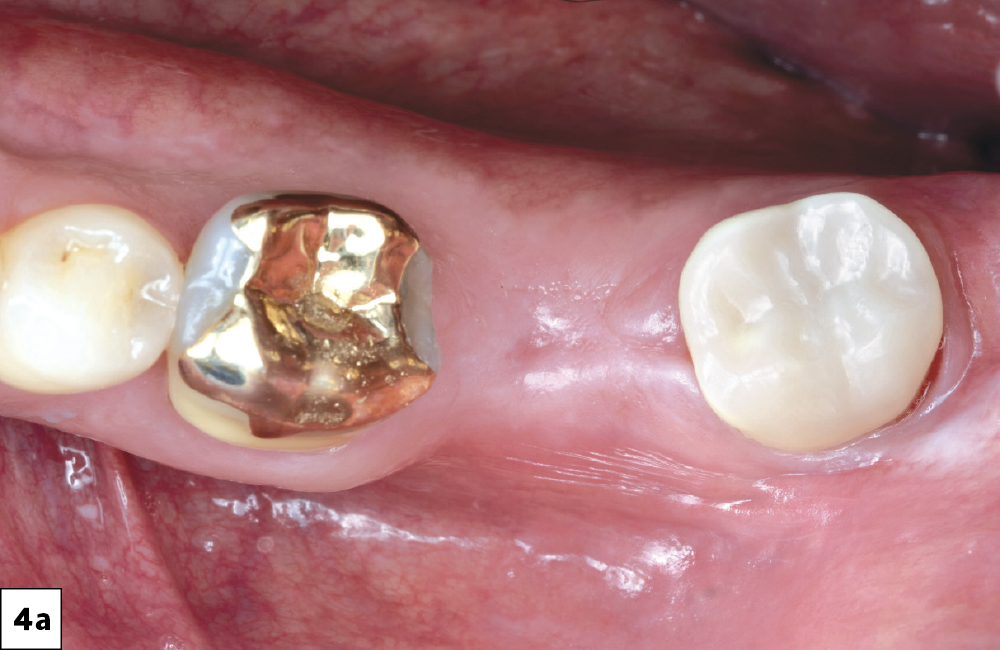

In-office milling is a quickly evolving option for the modern dental practice. With the introduction of a same-day screw-retained option, BruxZir® NOW SRC milling blocks, there’s even more opportunity for optimizing single-unit restoration workflows. In this case study, I’ll demonstrate how this product can be used as part of an efficient workflow for tooth replacement in the posterior. When combined with guided surgery and in-office crown design, this procedure offers reliable results while saving money and significantly cutting down on chair time for dentists.